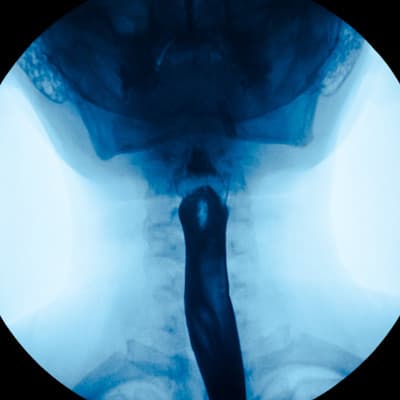

From examining a broken leg to diagnosing pneumonia in the lungs, X-rays can be used from head to toe for many purposes. If your child’s physician needs a closer look at their esophagus, stomach or small intestine, they may need one of the following digestive health tests:

An esophagram, which takes pictures of their esophagus

An upper GI, which takes pictures of their esophagus, stomach and the connection between their stomach and small intestine

Before the radiologist takes the X-ray, your child will need to drink a milkshake-like drink that contains Barium, which enables the doctor to see the structures of their digestive system on the images.